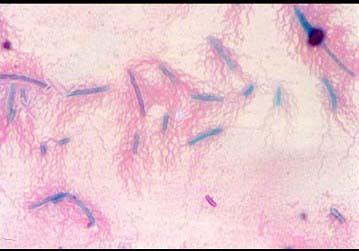

- 多项选择题对于如图所示细菌的描述中,正确的是 ( )

A、该细菌为球菌

B、该细菌为杆菌

C、该菌具有周鞭毛

D、该菌动力试验为阳性

E、该菌动力试验为阴性